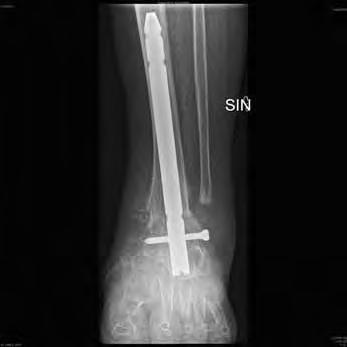

4) En instabil och icke belastningsbar fotled behöver stabiliseras medelst artrodes i syfte att förebygga amputation (Figur 6a-d).

harcotfotled höger. Figur 7b: Spikartrodes med fibrös läkning efter 20 veckor. Figur 7c: Smärtfri och belastningsbar fot